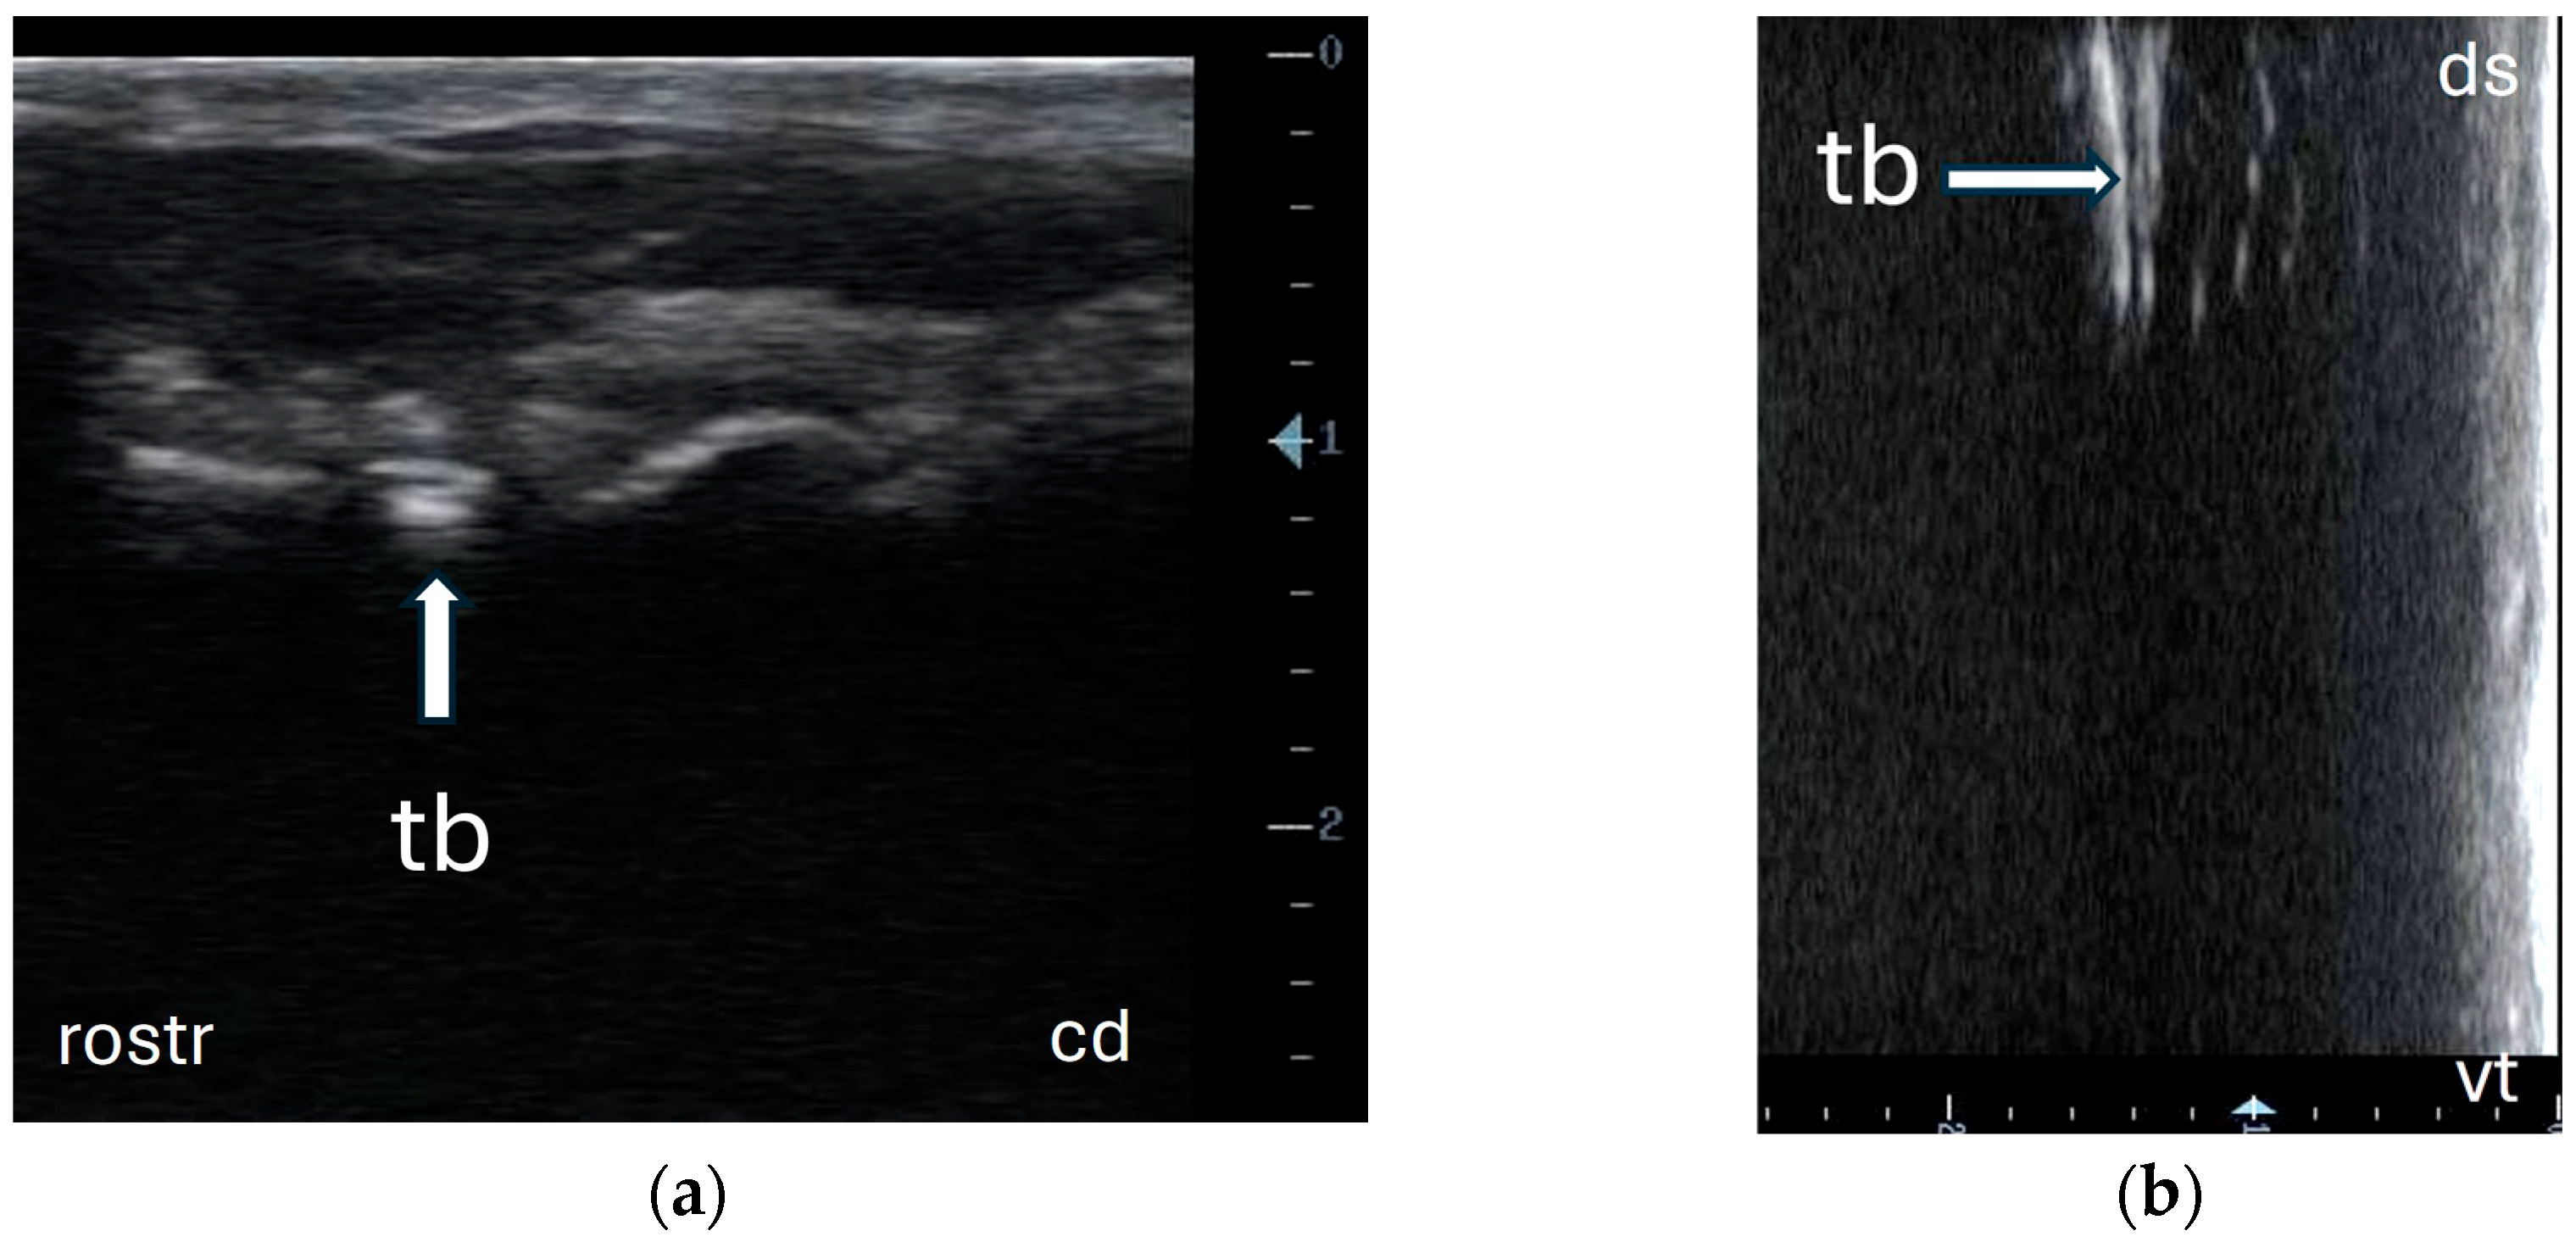

3.1. Identification of Anatomical Structures During Dissection and Ultrasonographic Appearance of Tympanic Bulla and Surrounding Structures in Cadaver Specimens

3.2. Ultrasonography of Tympanic Bulla and Surrounding Structures in Live Llamas and Alpacas and Measurement of Sonographically Visible Length of Bulla Wall